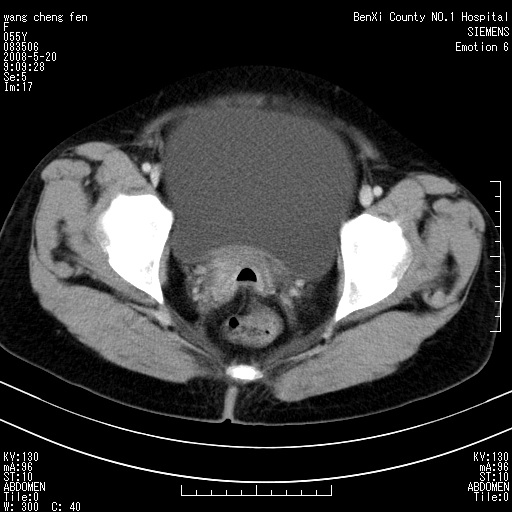

女、绝经后阴道流血3个月

左侧附件区可见一囊性占位,边缘清楚,内可见不规则形软组织影 ce:囊壁及内部可见强化 考虑 卵巢囊腺瘤

左侧附件区巨大囊实性病灶,边缘光整,病灶囊壁较厚,增强示囊壁及实性部分明显强化,强化呈度与宫体实质大致相同,宫腔积液征像,未见盆腔积液等其他异常,考虑左侧卵巢囊腺癌,不除外囊腺瘤及浆膜下肌瘤坏死

左侧附件区巨大囊实性病灶,边缘光整,病灶囊壁较厚,增强示囊壁及实性部分明显强化,强化呈度与宫体实质大致相同,宫腔积液征像,未见盆腔积液等其他异常。绝经后阴道流血3个月,结合病史左侧卵巢囊腺癌首先考虑,宫腔扩大不除外累及。期待结果。

支持浆膜下子宫肌瘤.之前由于网络原因未看全图片,现在重看,宫颈见一类圆形低密度影,增强轻度强化,低于肌层强化,宫腔扩大,考虑宫颈癌伴宫腔积液可能性大.